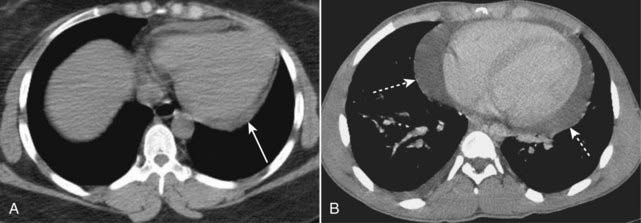

image

Figure 9-26 Aortic aneurysm, conventional chest radiograph and CT.

Close-up view of a frontal radiograph of the chest (A) demonstrates a large mediastinal soft tissue mass (solid white arrow). This soft tissue density represents a large aneurysm of the proximal descending aorta seen also in the CT scan (B). The aneurysm measured 6.7 cm, which placed it at significant risk for rupture. Calcification in the wall of an aneurysm is common (dotted white arrow). Contrast material mixes with blood flowing in the lumen of the aorta (solid white arrow), but the flowing blood is separated from the intimal calcification by a considerable amount of noncontrast-containing thrombus adherent to the wall (closed black arrow).